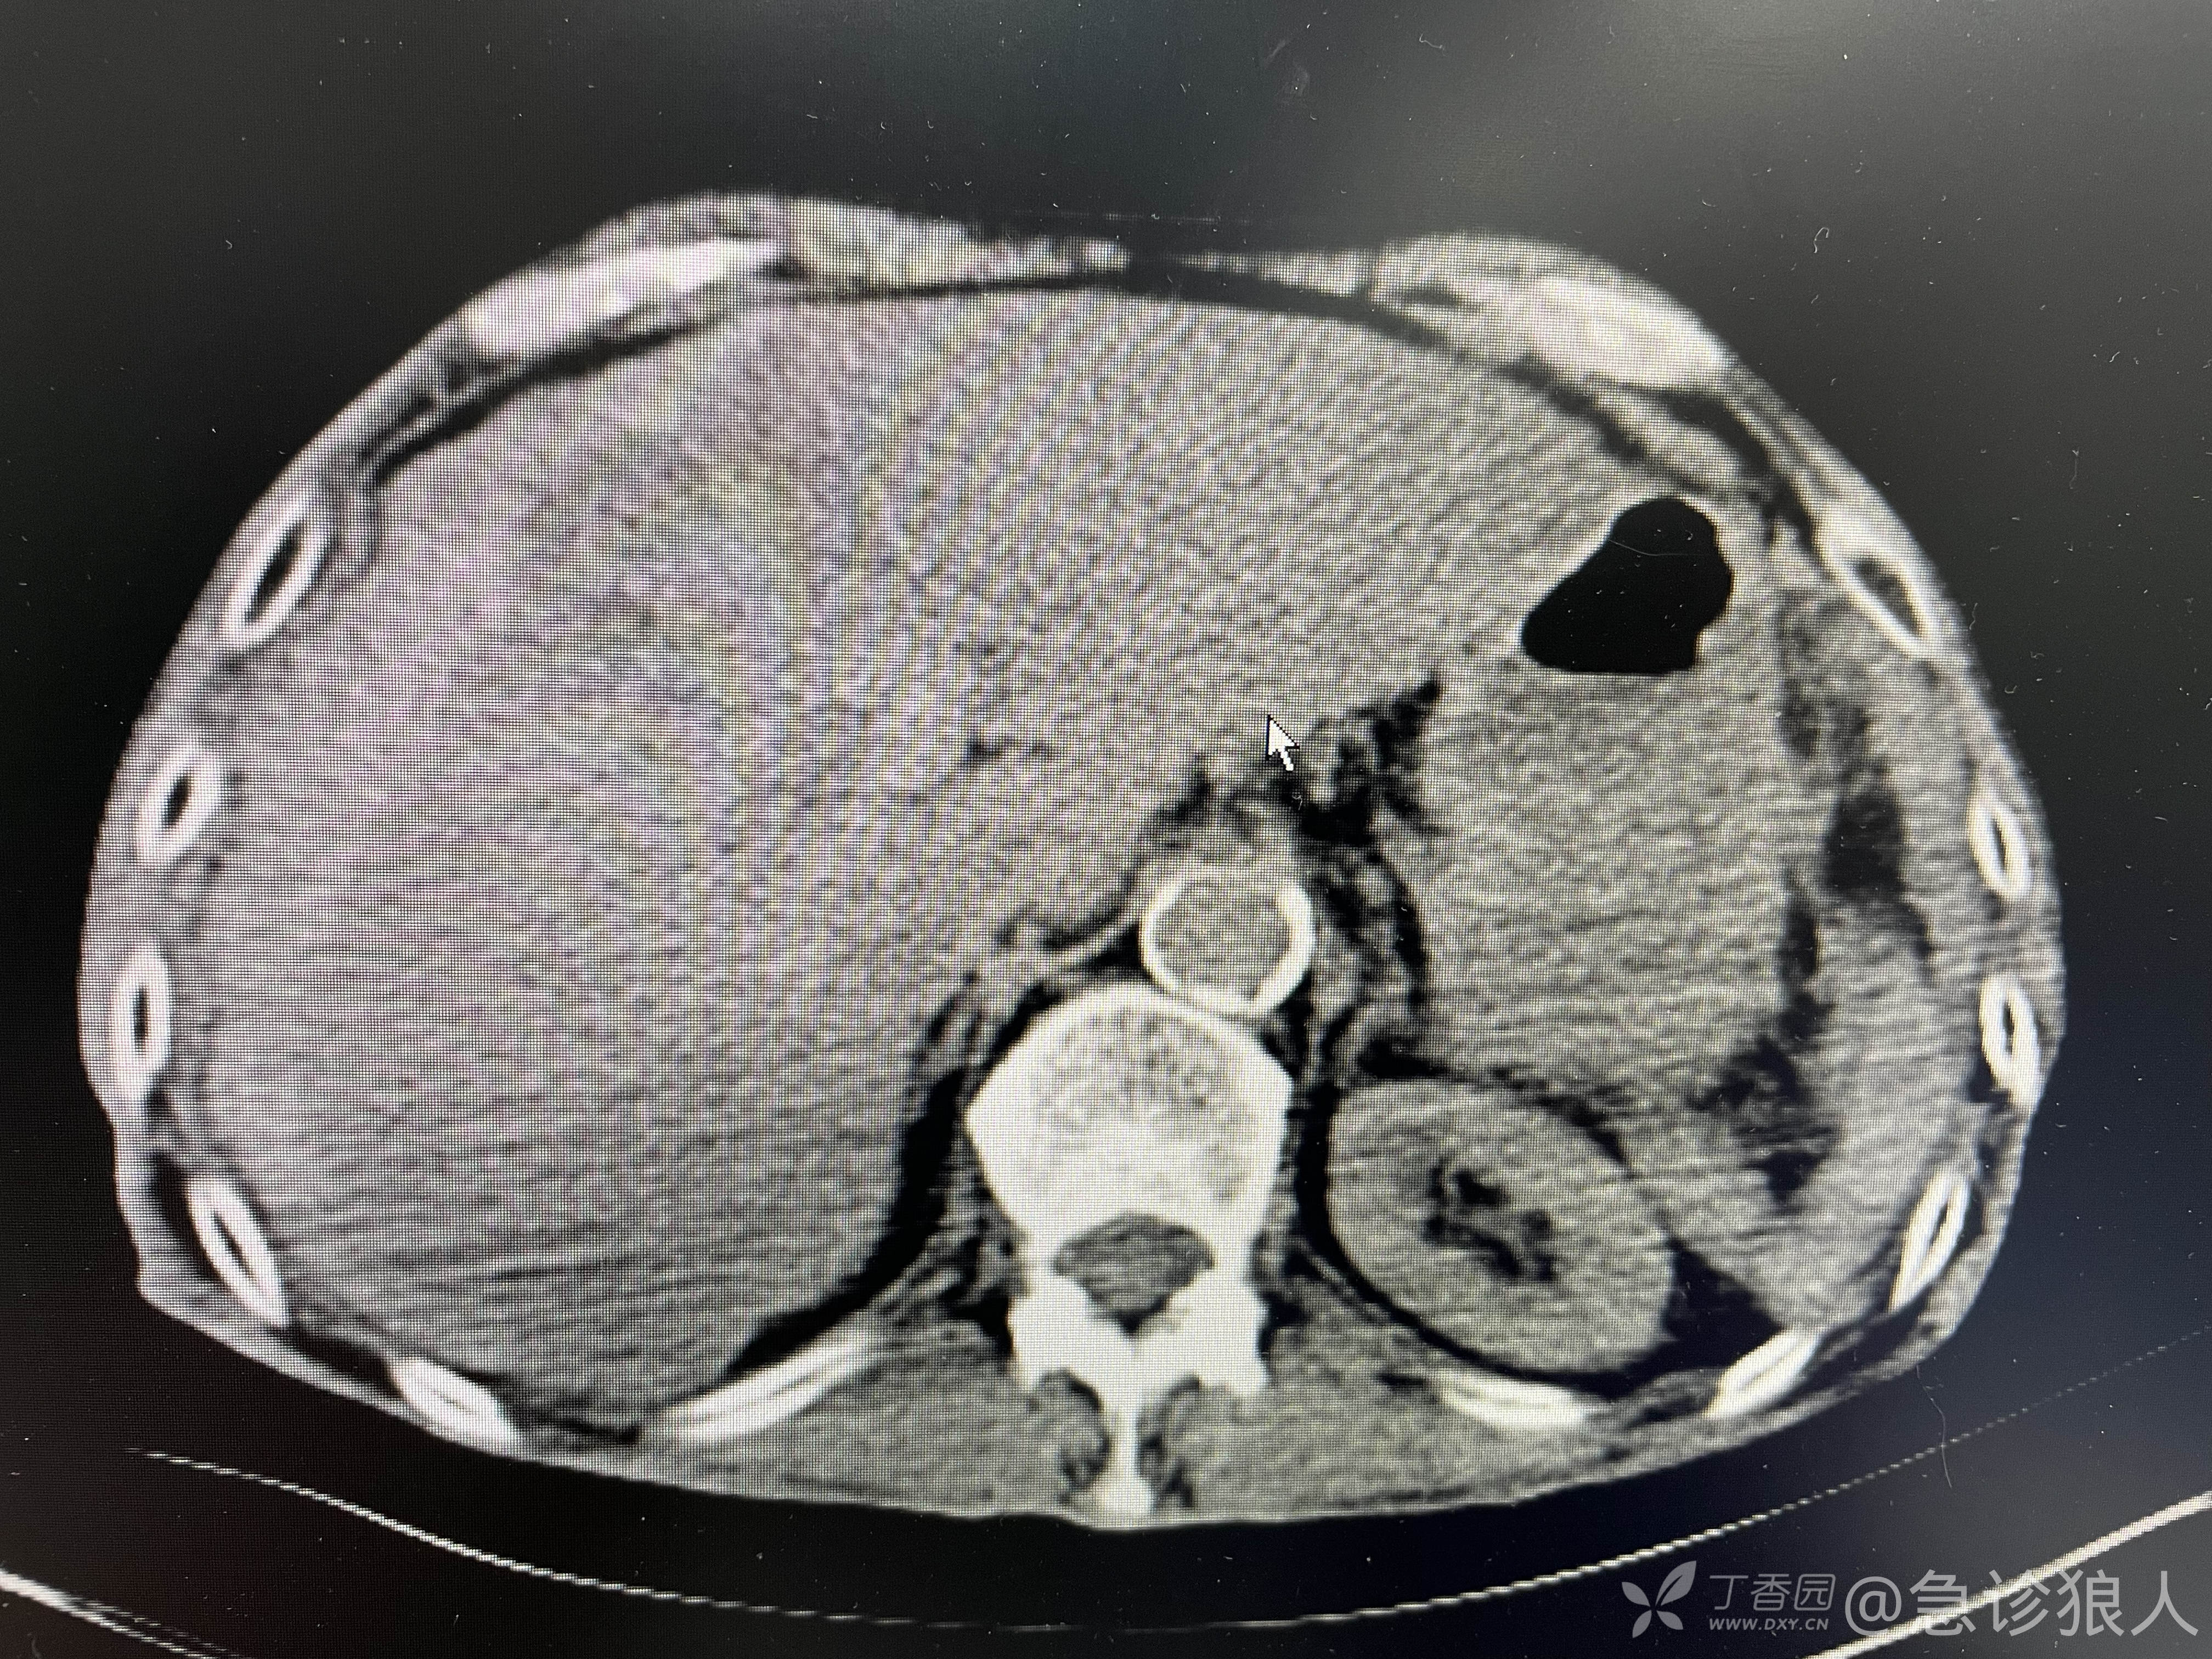

继续说,“你看老人肝脏,结构已经改变,肝功能很差了。你把检查该完善的完善了,我就要!”

“腹部Ct你要给做了吧,你这Ct就扫到胸部。不做腹部你也要给Ct室打电话,让把这部分Ct结果出了吧?”

“肝脏上有没有占位,结构改变了,肝硬化了?”

“我只能报脂肪肝,看不出来其他!”

“也不是这么说,我给你们讲讲他现在的情况。头晕、憋气、恶心、呕吐、腹痛,症状涵盖了神经系统、消化系统、呼吸系统。看他CT肺气肿,肯定老慢支有了。腹部Ct,肝脏结构变了,脂肪肝这么重,还这么瘦,应该是个酒精肝,肝硬化,平时喝酒很多吧?”

恶心、呕吐、头晕,这不就是喝多了!憋气是老慢支,腹痛是因为酒精肝肝硬化腹水,隐隐地痛。所有的检查都能解释!

快步走回诊室,“你爸没事了,就是个酒精肝,肝硬化,肝病的晚期,这次应该是偷喝酒了,喝多了。”